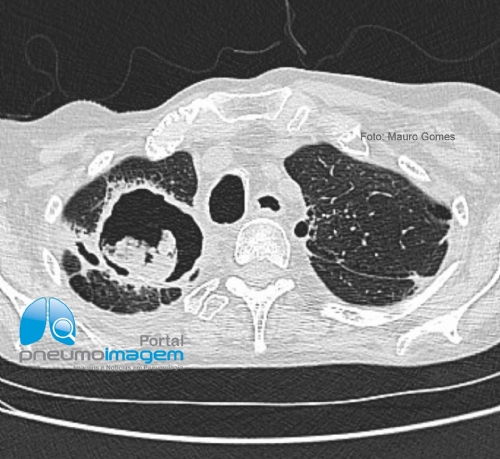

CASO CLÍNICO #55Homem de 52 anos portador de DPOC e com inapetência, fadiga, tosse e perda de peso nos últimos 4 meses. Antecedente de tratamento de Mycobacterium kansasii por 18 meses há 2 anos. Qual o diagnóstico? Deixe seus comentários abaixo.

A 52-year-old man with COPD and with inappetence, fatigue, cough and weight loss in the last 4 months. A history of treatment of Mycobacterium kansasii for 18 months 2 years ago. What is the diagnosis? Write your comments below.